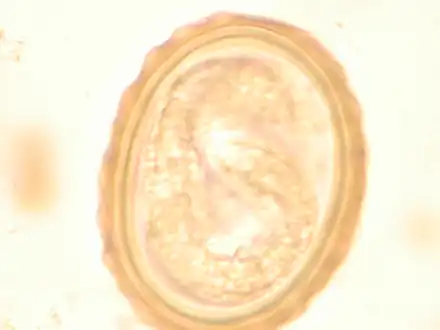

- The larva of Ascaris lumbricoides developing in the egg

- Ascaris egg, incubation process: The Ascaris egg incubation process consists of placing the egg in a controlled environment, at 26 °C (79 °F) during 28 days, in acidic conditions. This process allows for the evaluation of an egg to determine if it is viable or not.

Most diagnoses are made by identifying the appearance of the worm or eggs in feces. Due to the large quantity of eggs laid, diagnosis can generally be made using only one or two fecal smears.[31] The diagnosis is usually incidental when the host passes a worm in the stool or vomit. The eggs can be seen in a smear of fresh feces examined on a glass slide under a microscope and there are various techniques to concentrate them first or increase their visibility, such as the ether sedimentation method or the Kato technique. The eggs have a characteristic shape: they are oval with a thick, mamillated shell (covered with rounded mounds or lumps), measuring 35–50 micrometer in diameter and 40–70 in length. During pulmonary disease, larvae may be found in fluids aspirated from the lungs. White blood cell counts may demonstrate peripheral eosinophilia; this is common in many parasitic infections and is not specific to ascariasis. On X-ray, 15–35 cm long filling defects, sometimes with whirled appearance (bolus of worms).